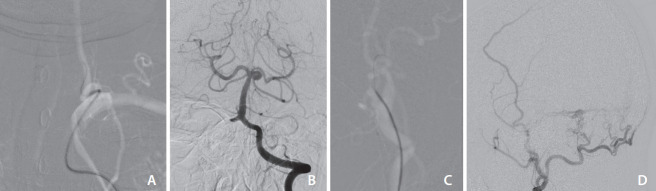

The fluoroscopy time was significantly shorter in the Catheter 3.0 group, which suggests that the processes under the fluoroscopy (navigation of the guidewire or catheter advancement) consumed less time with the Catheter 3.0 system. It can also be interpreted that the catheter could be placed in the desired location faster and probably with fewer attempts considering the smaller number of catheters and guidewires used in the Catheter 3.0 group. Additionally, the guidewire that was left in the catheter during contrast injection may have stabilized the catheter even in the unstable position and reduced the chances of excessive catheterization, catheter kickback, and contrast reflux (Fig. 3). The fluoroscopy dose of the Catheter 3.0 system was also significantly less, which is an expected result because the fluoroscopy dose would be proportional to the fluoroscopy time if other conditions were constant.

Fig. 3.

Representative cases using the Catheter 3.0 system in tortuous vessels. (A) A patient had a marked tortuosity in the supraaortic neck vessel, which prevented stable and safe catheterization of the left vertebral artery. The guidewire leading in front of the catheter prevented the wedging of the catheter tip against the vessel wall and kickback of the catheter during contrast injection. (B) Despite flow competition from the contralateral vertebral artery, the aneurysm at the superior cerebellar artery origin of the basilar artery was well-visualized on the left vertebral arteriogram. (C) Catheterization of the left external carotid artery with marked tortuosity. The guidewire that entered the occipital artery guided the catheter toward the occipital artery without dislodging during contrast injection. (D) Good opacification of the feeders of the sigmoid sinus dural arteriovenous fistula arising from the occipital and middle meningeal arteries.